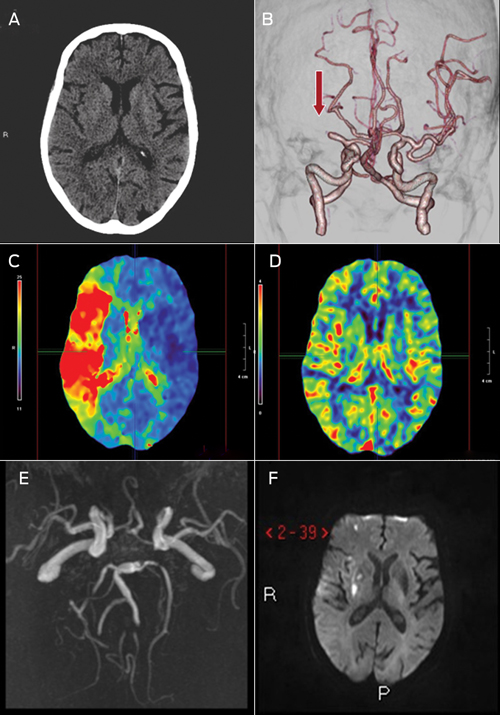

After Catherine’s initial clinical assessment, she proceeded to non-contrast CT of her head, which showed no acute ischaemic changes. Perfusion CT (CTP) and CT angiogram (CTA) were then carried out, which confirmed that she had a mid-M1 segment occlusion of the right middle cerebral artery. Despite minimal infarcted cerebral tissue, the whole of the middle cerebral artery territory was at risk (ie, there was an ischaemic penumbra) (Box 1).

On review the next day, Catherine had no focal neurological deficit, and complete reperfusion and minimal infarction were shown on MRI (Box 1). She was commenced on long-term warfarin therapy. She was reviewed by allied health staff to check on her cognition, mobility and self-care activities, to ensure that it was safe for her to be discharged home. On Day 5, she was back to her premorbid level of functioning and was discharged.

1 Multimodal computed tomography (CT) and magnetic resonance imaging (MRI) images of Catherine’s brain before and after treatment with recombinant tissue plasminogen activator

A: Non-contrast CT showing no acute changes, as is often the case in acute stroke.